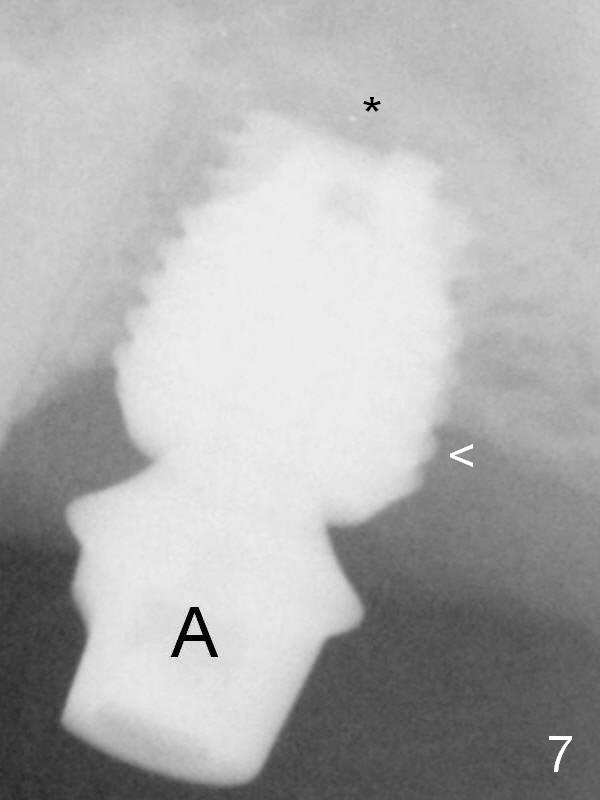

When the patient returns for impression 6.5 months postop, the provisional has dislodged because of the short abutment (Fig.7 A (6.5x4(2) mm). A longer one is placed (6.5x5(3) mm). The original sinus floor has been resorbed, while there is bone formation apical to the implant (*). Two distal threads are not covered by the bone. Therefore the implant should have been placed higher. There is a distinct layer of bone apical to the implant 22 months post cementation (Fig.10 *). The implant remains infection free 3 years 10 months post cementation (Fig.12) due to the thick gingiva and good oral hygiene.